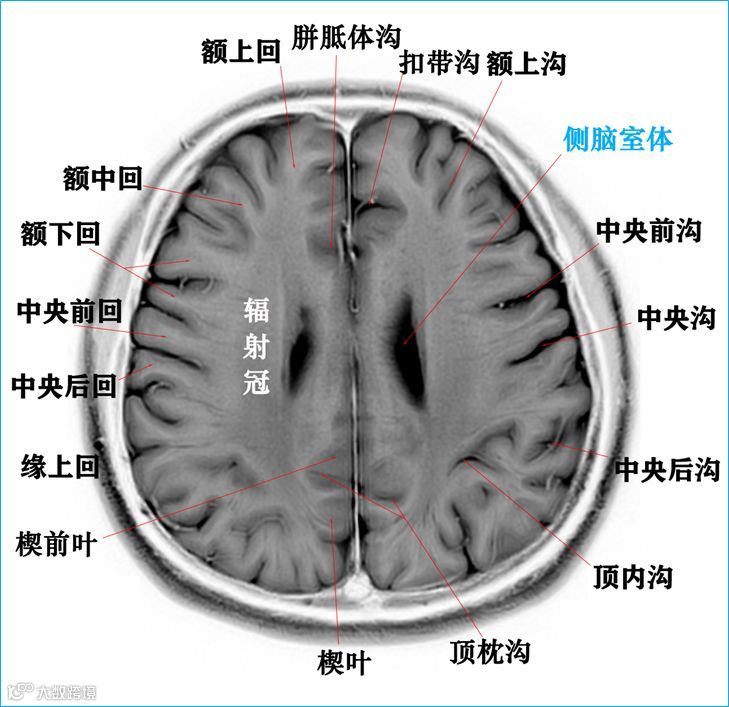

在T2WI反相图学下的颅脑断层解剖(吴晓安老师亲自手动标准)以及标本断层解剖,满满干货,坐在小板凳上,一起学习吧……